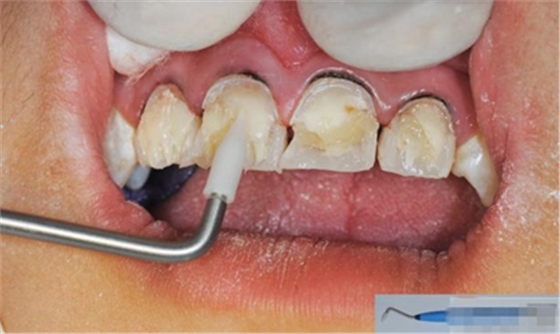

【檢查】12,11,21,22,均行玻璃離子充填,各牙不同程度部分充填物脫落,探(—),叩(—),冷刺激無反應(yīng),無松動(dòng),牙齦顏色粉紅,質(zhì)地堅(jiān)實(shí)而有彈性,點(diǎn)彩正常,牙結(jié)石(—);牙髓活力測試無反應(yīng)。

【診斷】12,11,21,22牙體缺損

【纖維樁制作】

制作 背板

修復(fù)鄰壁

修整纖維樁長度

取出纖維樁,按所需長度裁截纖維樁 在有水條件下 用切割砂片或車針截取纖維樁,切勿使用鉗子,剪刀或鑷子以免破壞樁的結(jié)構(gòu)